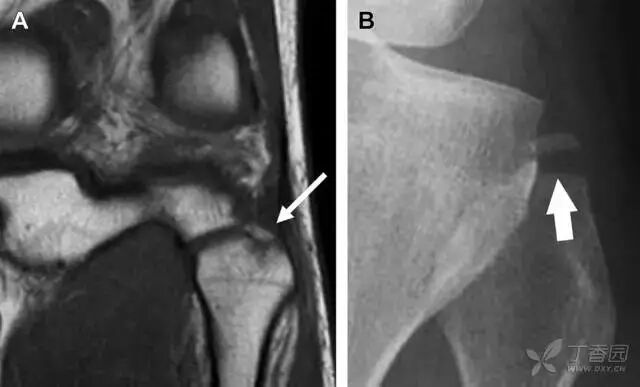

06股骨颈应力性骨折

股骨颈应力性骨折在参加耐力运动的运动员中常见,且常发生在股骨颈压力侧。股骨颈基底部发现一垂直于骨皮质的线性硬化带可诊断这种类型的疲劳性骨折(图 8)。

图 8 长跑运动员股骨颈应力性骨折。X 片(A)和冠状位 CT 多维重建(B)图像示穿过股骨颈内侧皮质中的透亮区(箭头),周围硬化。骨折垂直于皮质

股骨颈张力侧的应力性骨折有可能发展为完全骨折(图 9)。

图 9 进食障碍患者股骨颈应力性骨折的张力侧。A 正位片示股骨颈完全骨折。B 2 周前的 X 片示局部骨量减少,正是后来发生骨折的位置(箭头)